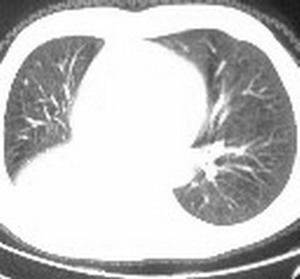

标题: CT6943:[讨论]胸部,M/67Y,体检发现。 [打印本页]

标题: CT6943:[讨论]胸部,M/67Y,体检发现。

右肺下叶支气管阻塞,右下叶不张,考虑中心型肺癌伴下叶不张

先考虑:右下肺中心型肺癌伴下叶肺不张、胸腔积液

右肺下叶支气管闭塞,中间段支气管狭窄,下叶不张,胸腔及叶间积液.中心型肺癌伴下叶肺不张.胸腔和叶间积液.

右肺下叶支气管闭塞,伴下叶实变不张。建议增强及纤支镜。

右肺下野后部均匀低密度影,边缘锐利,前缘外突(不支持肺不张),纵隔内未见明显肿大淋巴结,右下肺门结构显示欠清,临床资料太过简单,考虑右侧后胸部包裹性积液。其他待排。建议密切结合临床其他检查。